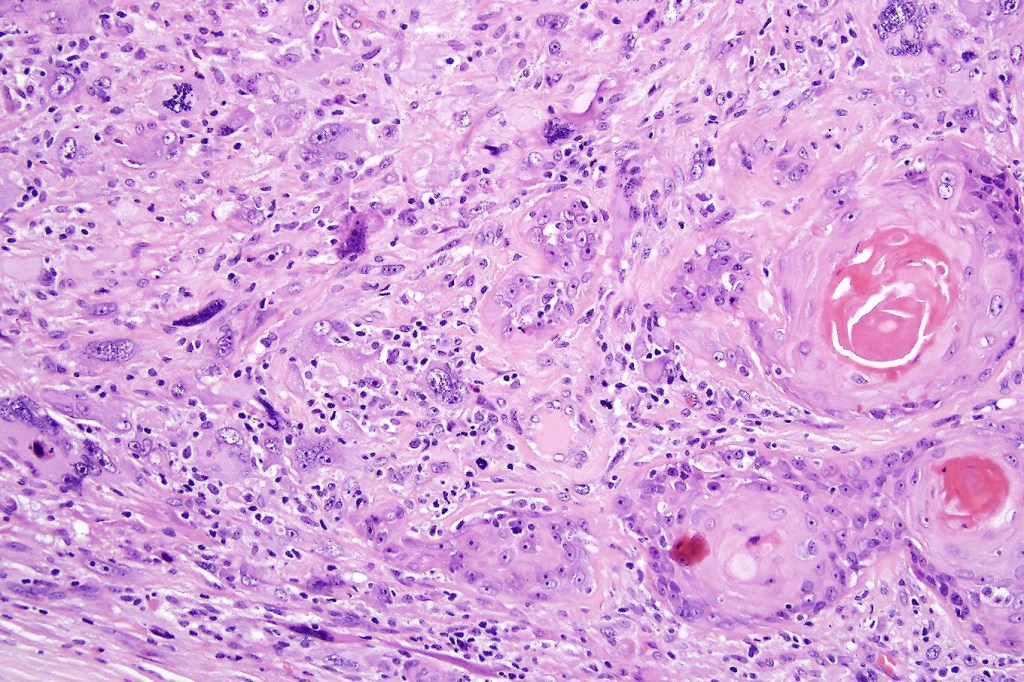

•Admixture of squamous carcinoma & pleomorphic spindled cell, osteoid, chondroid, MFH-like +/- osteoclast-like giant cells & rarely, smooth muscle, skeletal muscle, myofibroblastic or angiosarcomatous elements

•Mesenchymal element variable CD10, CD68, CD99 & lineage specific markers +ve; scattered cells may show weak keratin expression